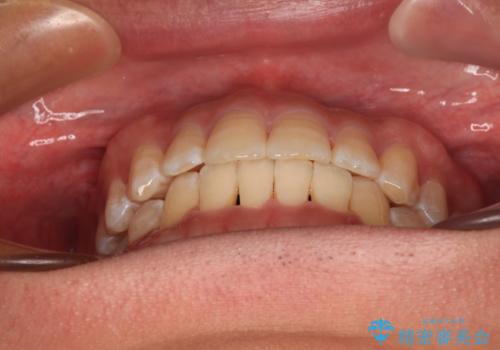

予定していた期間より長くかかりましたが、1年強できれいな歯列に仕上がりました。